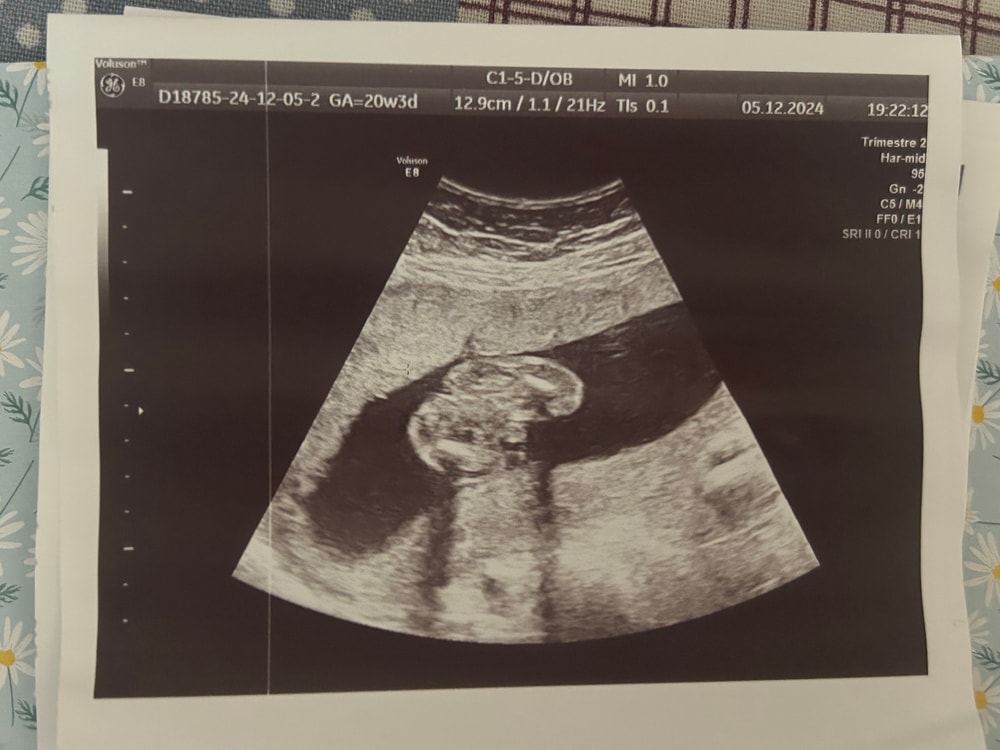

Arina в Клуб беременных 8 месяцев Пол малыша. Тут 20-21 нед🐣 Пол малыша Всем привет! Подскажите, пожалуйста 🙏🏻 это ведь мальчик? :) Посмотрите еще 20 записей на эту тему Лучший ответ Мама Лиля Пацан 23.03.2025 Ответить Отменить Ответить Лера Это мальчик 23.03.2025 Ответить Ольга На девочку похоже, если я правильно вижу))) 23.03.2025 Ответить Ольга Ольга , хотяяяяяя.... На последней фотке мальчик 23.03.2025 Ответить Сабрина я не разбираюсь, но интуитивно кажется что мальчик 🤔 23.03.2025 Ответить Лариса Тоже кажется, что мальчик. А врач кого предположил? 23.03.2025 Ответить Светлана По последней фотке- мальчик 23.03.2025 Ответить Пришел анализ на определение пола 😍 Пол ребенка Чаты Беременных Выберите чат: Январята-2026 Февралята-2026 Мартята-2026 Апрелята-2026 Майчата-2026 Июнята-2026 Июлята-2026 Августята-2026